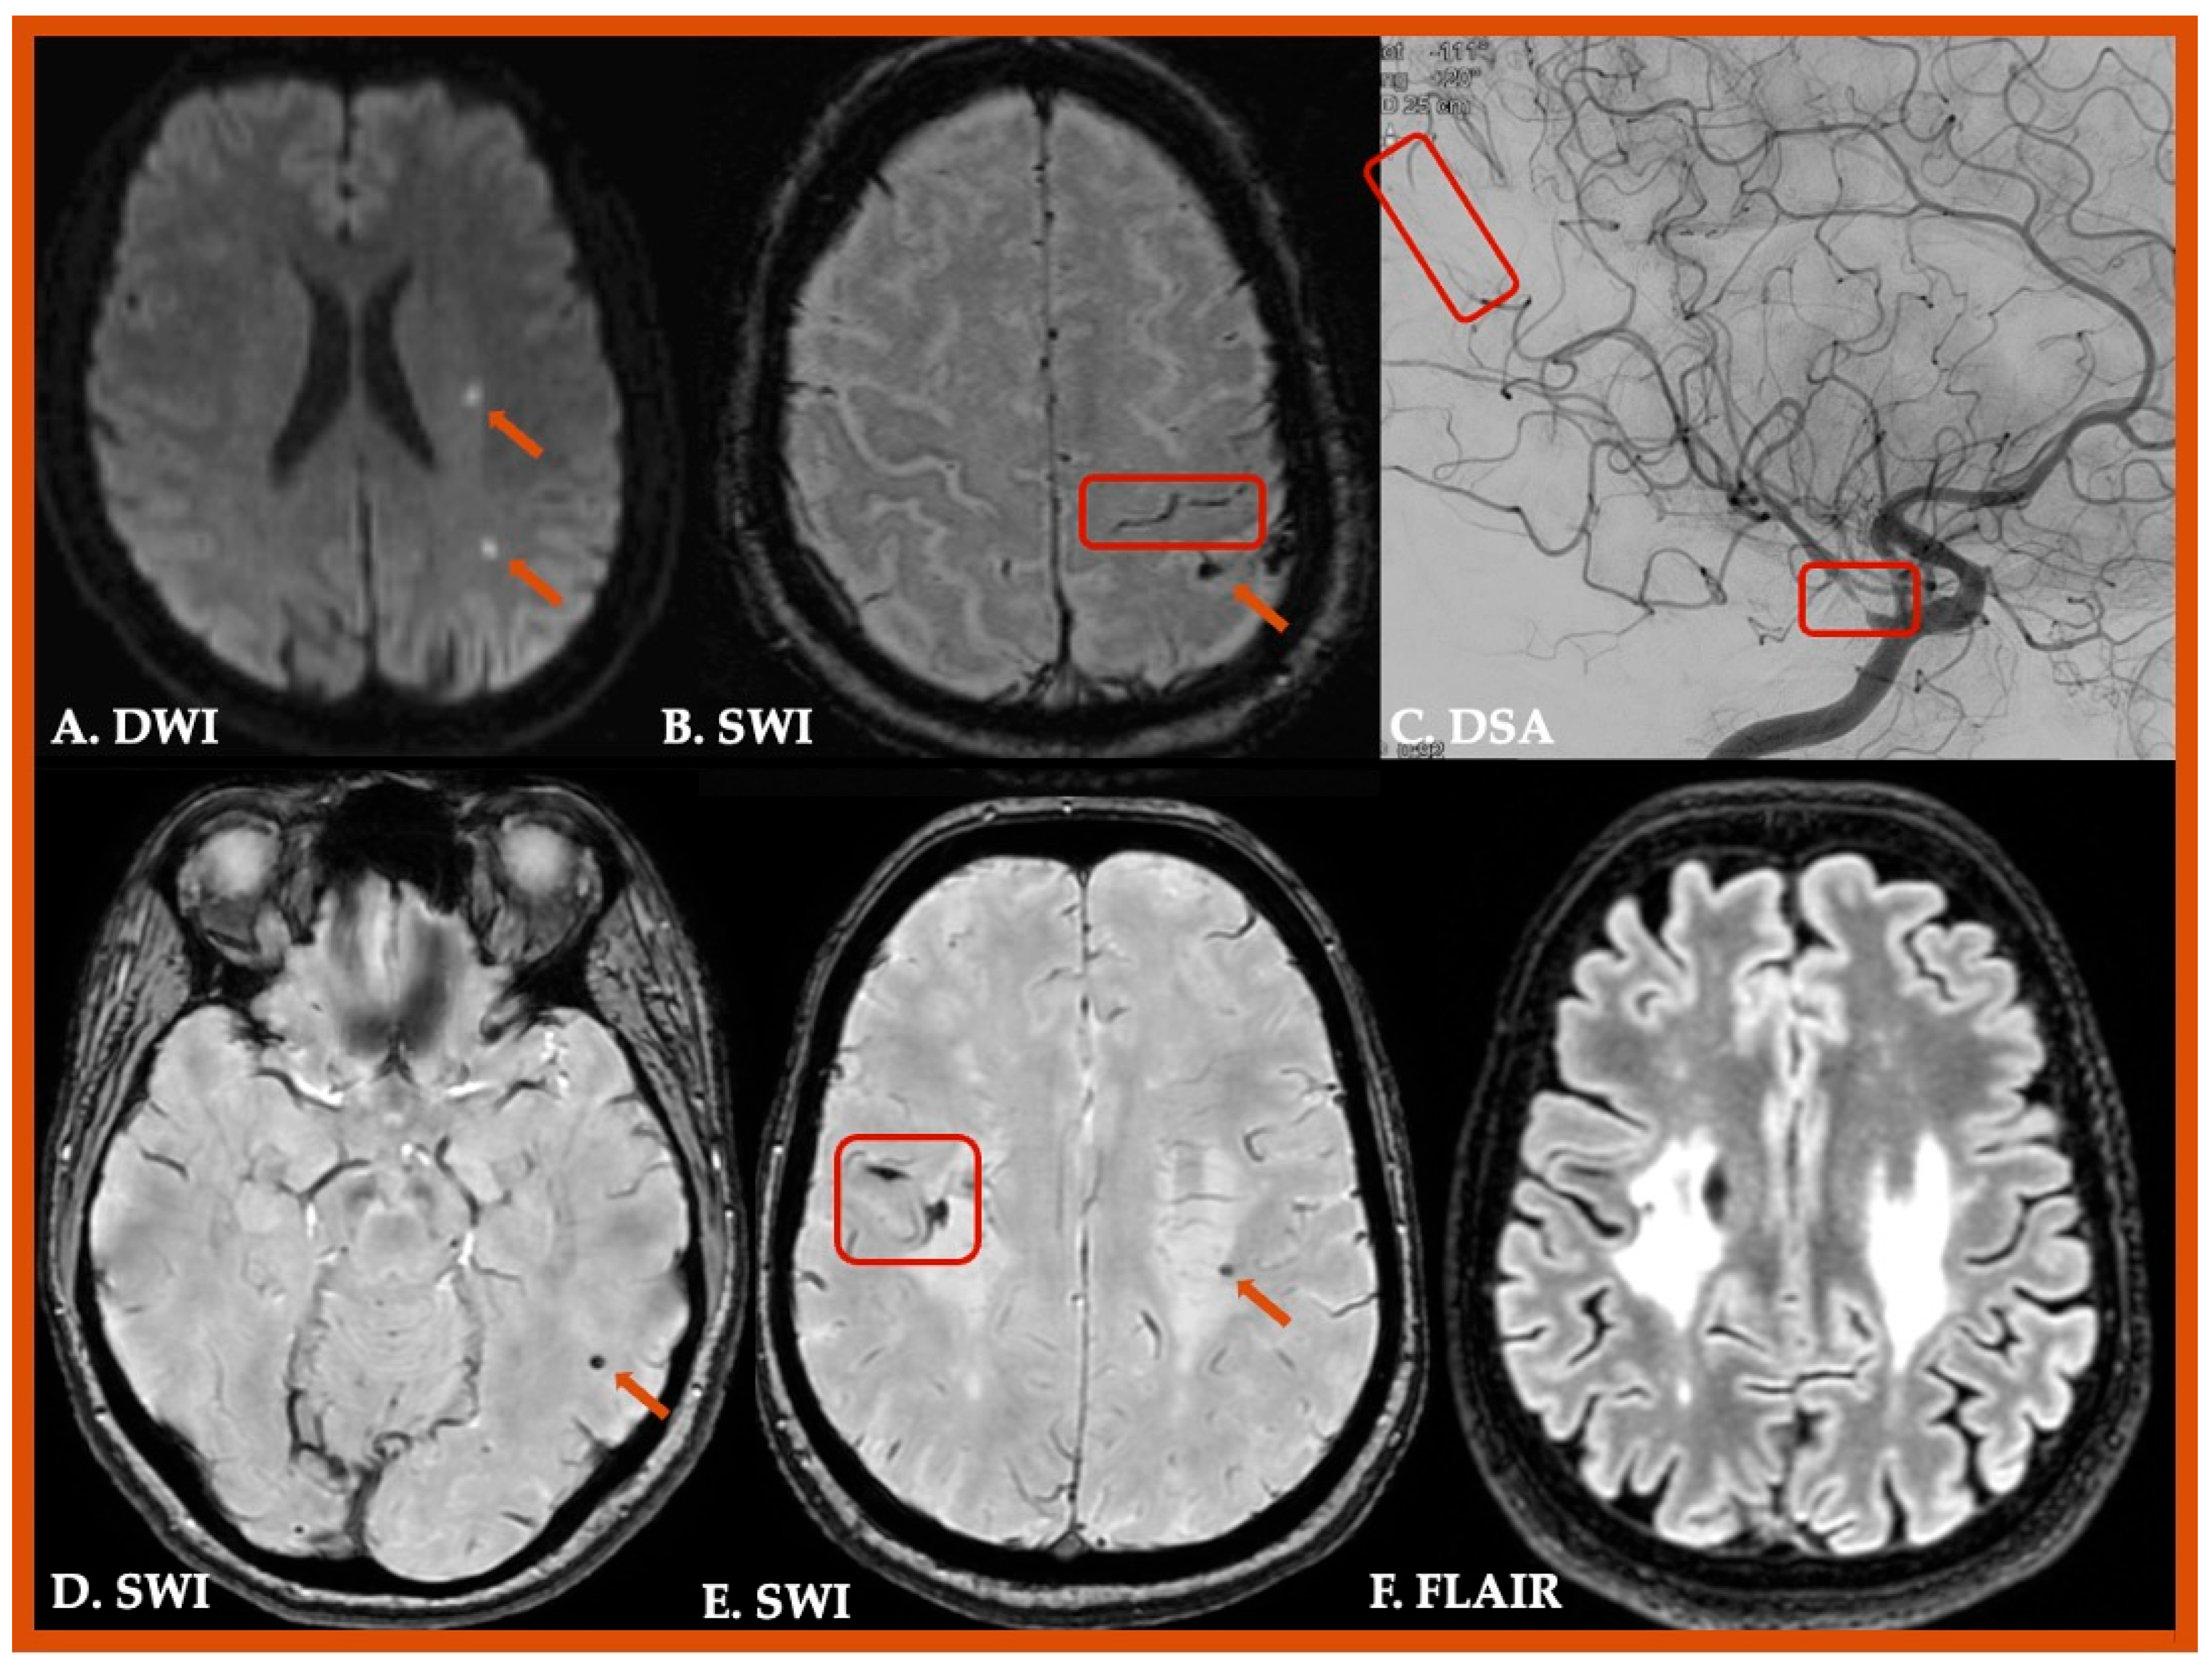

| 3. Probable CAA | Clinical data and MRI demonstrating the following: • Age ≥ 50 years • Presentation with spontaneous ICH, TFNEs, or CI/Dementia • ≥2 of the following strictly lobar hemorrhagic lesions on T2*-weighted MRI, in any combination: ICH, CMB, cSS/cSAH foci OR • 1 lobar hemorrhagic lesion + 1 white matter feature (Severe CSO-PVS or WMH-MS) • Absence of any deep hemorrhagic lesions (ICH, CMB) on T2*weighted-MRI • Absence of other cause of hemorrhagic lesions * • Hemorrhagic lesion in cerebellum not counted as either lobar or deep hemorrhagic lesion |

| 4. Possible CAA | Clinical data and MRI demonstrating the following: • Age ≥ 50 years • Presentation with spontaneous ICH, TFNEs, or CI/Dementia • Absence of other cause of hemorrhage * • 1 strictly lobar hemorrhagic lesion on T2*-weighted MRI: ICH, CMB, cSS/cSAH focus OR • 1 white matter feature (Severe CSO-PVS or WMH-MS) • Absence of any deep hemorrhagic lesions (ICH, CMB) on T2*-weighted MRI • Absence of other cause of hemorrhagic lesions * • Hemorrhagic lesion in cerebellum not counted as either lobar or deep hemorrhagic lesion |